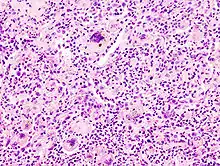

A giant cell (also known as a multinucleated giant cell, or multinucleate giant cell) is a mass formed by the union of several distinct cells (usually histiocytes), often forming a granuloma.[1]

Non-osteoclast MGCs can arise in response to an infection, such as tuberculosis, herpes, or HIV, or as part of a foreign body reaction. These MGCs are cells of monocyte or macrophage lineage fused together. Similar to their monocyte precursors, they can phagocytose foreign materials. However, their large size and extensive membrane ruffling make them better equipped to clear up larger particles. They utilize activated CR3s to ingest complement-opsonized targets. Non-osteoclast MGCs are also responsible for the clearance of cell debris, which is necessary for tissue remodeling after injuries.[2]

Langhans giant cells are named for the pathologist who discovered them, Theodor Langhans. Like many of the other kinds of giant cell formations, epithelioid macrophages fuse together and form a multinucleated giant cell. The nuclei form a circle or semicircle similar to the shape of a horseshoe away from the center of the cell. Langhans giant cell was typically associated with tuberculosis but has been found to occur in many types of granulomatous diseases.

Foreign-body giant cells form when a subject is exposed to a foreign substance. Exogenous substances can include talc or sutures. As with other types of giant cells, epithelioid macrophages fusing together causes these giant cells to form and grow.[13] In this form of giant cell, the nuclei are arranged in an overlapping manner. This giant cell is often found in tissue because of medical devices, prostheses, and biomaterials.